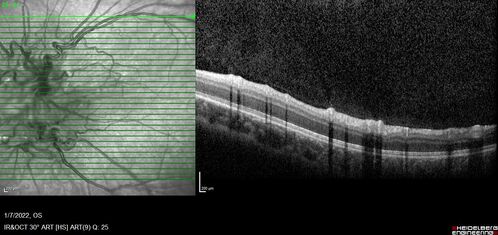

Combined hamartoma of the retina and retinal pigment epithelium

8 year old boy failed vision screening at school. VA 20/20 OD, 20/40 OS

Combined hamartoma of the retina and the retinal pigment epithelium